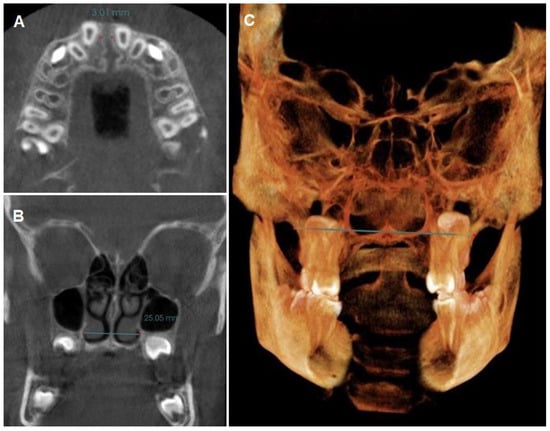

- Coronal perimeter (CP): the distance between the mesial of the right upper first molar and the mesial of the left upper first molar, passing through the vestibular side of all the teeth of the arch (Figure 2A).

- Angulation of the upper first molar (MA): the angle formed between a straight line drawn parallel to the hard palate plane (in sagittal view, utilizing the anterior nasal spine (ANS) and posterior nasal spine (PNS) as reference points) and a line passing through the center of the pulp chamber of both upper right and left first molars [12,55] (Figure 2C).

- Intermolar width (IMW): the distance between the central fossa of the upper right and left first molars was measured (Figure 2C).